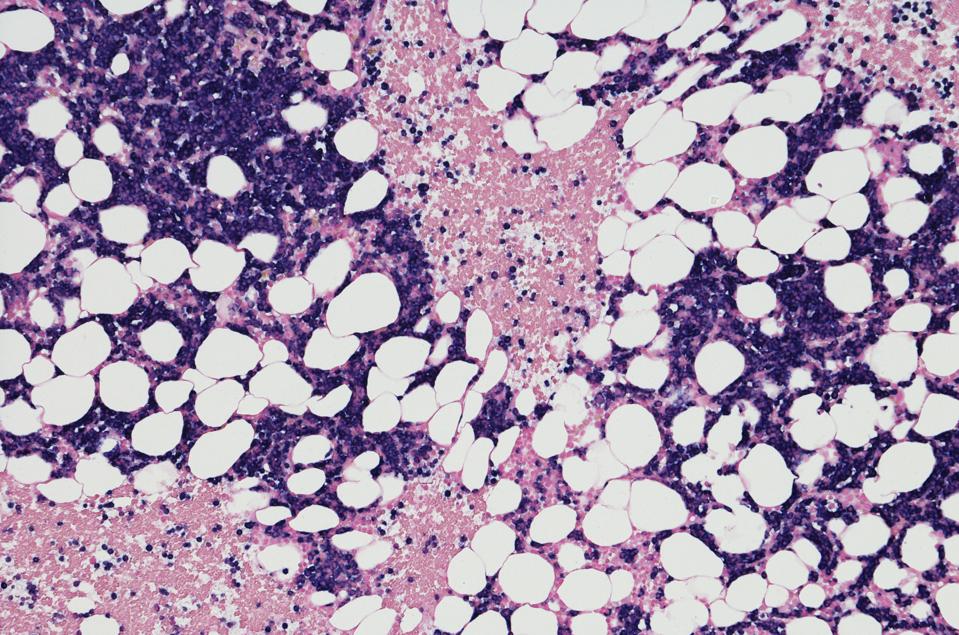

Micrograph of myeloma tumor from bone marrow biopsy

GETTY

Multiple myeloma (MM) is a cancer of the plasma cells in the bone marrow. This cancer initially responds well to chemotherapy, targeted therapy and other first line therapeutics. Unfortunately, the disease often returns and grows resistant to prior treatments. When other options are no longer effective, CAR T cells can achieve a durable response.